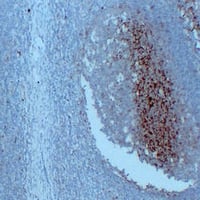

(Immunohistochemical analysis of CD14 staining in human spleen formalin fixed paraffin embedded tissue section. The section was pre-treated using heat mediated antigen retrieval with sodium citrate buffer (pH 6.0). The section was then incubated with the antibody at room temperature and detected using an HRP conjugated compact polymer system. DAB was used as the chromogen. The section was then counterstained with haematoxylin and mounted with DPX.)